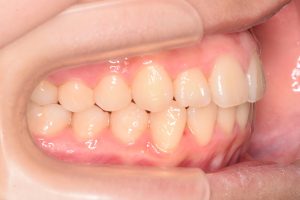

この患者さんは、初診時12才女性。

「上の前歯の中心がずれている」

「全体的に歯並びが良くないのが気になる」

ということで来院されました。

1期治療開始時(2024年3月)

右側